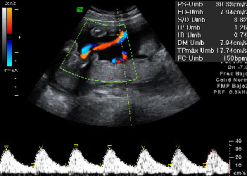

Ecografía de la semana 20 o morfológica, así se denomina esta prueba diagnóstica, considerada como la primera "foto" del bebé. Decimos esto porque el ecografista recorre con mucha calma y cautela todas las estructuras básicas y órganos del bebé, que a esta edad gestacional se suelen ver con claridad. El pequeño aún se mueve con soltura dentro del líquido amniótico, a veces esquivando la mirada del ecografista, algo que en pocas semanas hará con mucha más dificultad. Merece la pena ver esta galería de ecografías de la semana 20 (y alrededores, puesto que se puede hacer a partir de las semana 18) en 2D, 3D y 4D. En la eco de la semana 20 también pueden detectarse algunas malformaciones fetales, pero lo usual que que se compruebe la buena salud del feto.